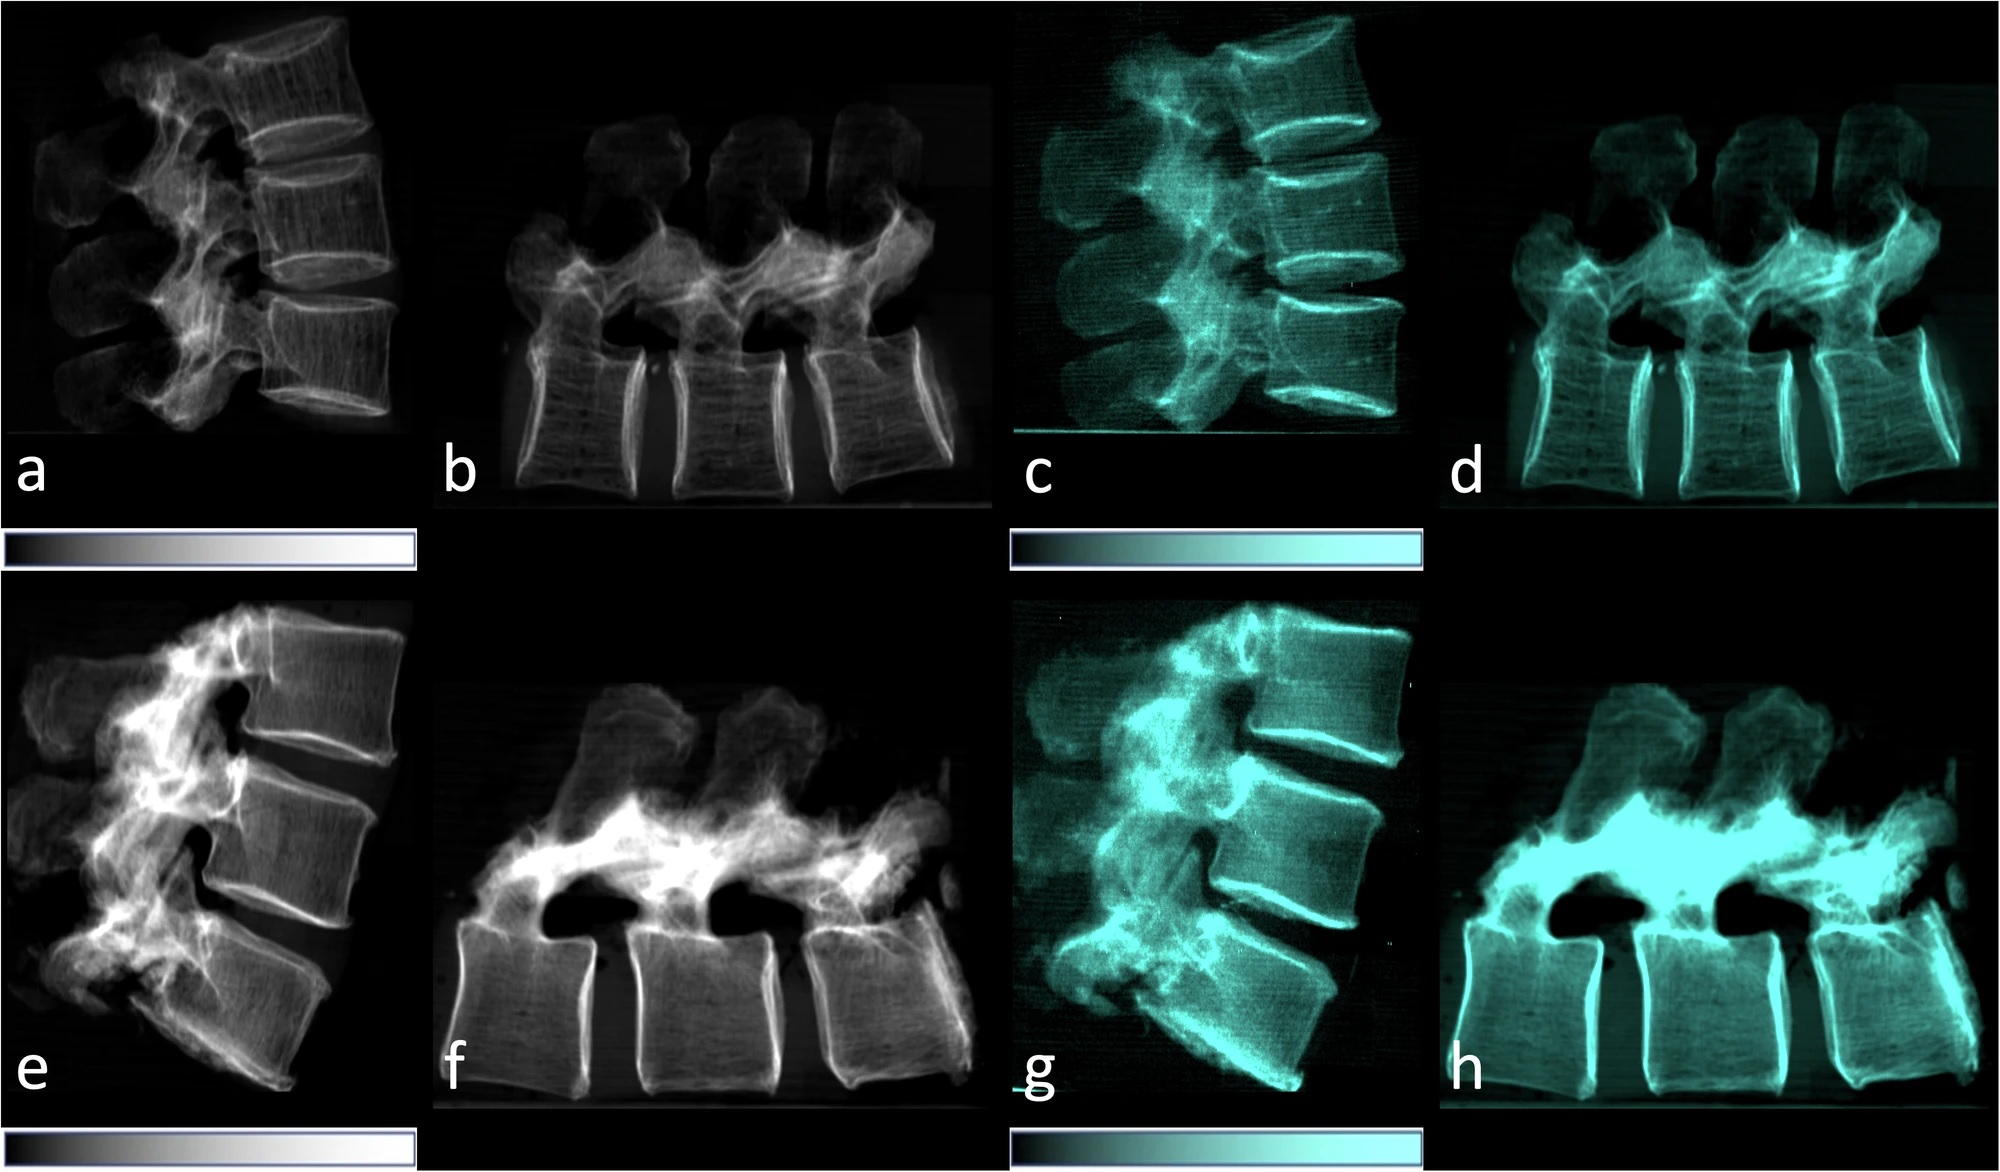

In attenuation-based radiography, dense structures generate a high signal, while in dark-field imaging, the small-angle scattering in lung tissue generates a high signal. Because dark-field x-ray imaging excludes unscattered photons, the space around the lungs appears dark (because there is no material there to scatter photons).

The researchers found normal human lungs on dark-field chest x-ray imaging produced high signal, while the surrounding osseous structures had low signal and soft tissue produced no signal. The average total dark-field signal intensity over all participants for the entire lung was (17 ± 4) × 10-3 m2 and the total signal demonstrated a positive correlation with lung volume (r = 0.61, p < 0.001).

Attenuation-based (left) and dark-field (right) posteroanterior radiographs of the thorax in example subjects. Images were obtained in (A, B) a 33-year-old man and (C, D) an 81-year-old man. The same window and level settings were applied within the respective modality. While attenuation-based images show attenuating structures, such as the bones and the soft tissue, dark-field images show the amount of tissue interfaces in the beam path. Image courtesy of Radiology."Because of the nature of signal generation in dark-field imaging, bone structures and soft tissue generate only a minimal dark-field signal compared with lung tissue. This feature allows for a detailed depiction of lung tissue without impairment by surrounding structures. We found that the quantitative x-ray dark-field coefficient based on the total dark-field signal and lung size is independent from the subject's characteristics," the researchers wrote.